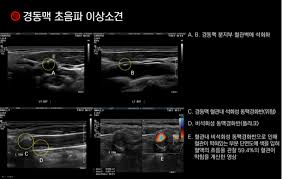

경동맥 초음파 검사로 알 수 있는 병 1: 경동맥 죽상경화증

경동맥 죽상경화증은 경동맥의 벽에 콜레스테롤이나 칼슘이 침착되어 두꺼워지는 병입니다. 경동맥 초음파 검사로 알 수 있

는 병 중 가장 흔한 질환으로, 경동맥의 내중막 두께(IMT)를 측정하여 동맥경화증의 진행 여부를 판단할 수 있습니다. IMT가 1mm 이상이면 동맥경화가 진행되고 있다는 것을 의미합니다. 이 질환은 뇌졸중의 위험 요소로 작용하므로 조기 진단이 중요합니다.